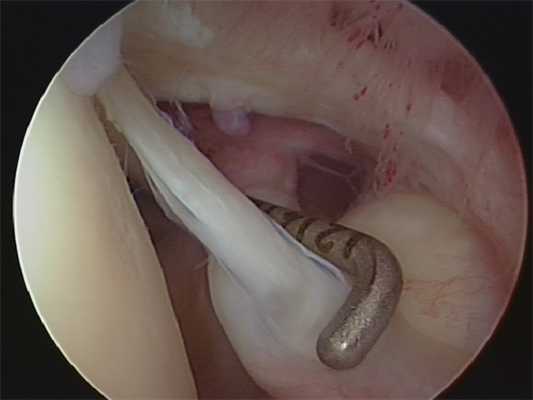

Операция выполняется под общей анестезией артроскопически. Это значит, что через один разрез кожи длиной около 1см в полость сустава будет введена видеокамера с источником света.

Затем производится осмотр всех важных структур и оценка их состояния. К этим структурам относятся хрящ суставных поверхностей, сухожилия капсулы сустава и вращательной манжеты. Важные находки могут быть зафиксированы в виде цифровой фотографии или видео HD-качества.

Иллюстрация: эндоскопия плечевого сустава

Поврежденные структуры восстанавливаются с использованием наиболее современных методик. К повреждениям, которые можно восстановить артроскопически, относятся: нестабильность, повреждения длинной головки двуглавой мышцы, адгезивный капсулит. Вторая часть операции производится в пространстве над головкой плечевой кости - в подакромиальном пространстве. Здесь находится причина хронического бурсита и повреждений сухожилий вращательной манжеты. После обработки хронического бурсита взгляду хирурга открываются многие важные элементы плечевого сустава. Дефекты сухожилий вращательной манжеты могут быть восстановлены при помощи швов и якорных фиксаторов. Кальцификат при кальцифицирующем тендините обнажается после обработки хронического бурсита и может быть легко удалён. Последним осматривается акромиально-ключичный сустав, артроз которого может причинять значительную боль при обычных бытовых нагрузках.

Иллюстрация: декомпрессия субакромиального пространства